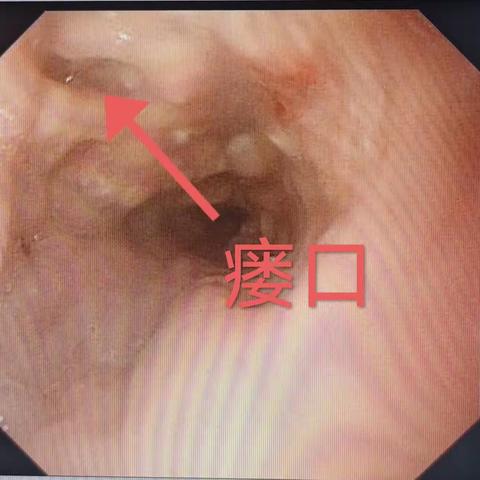

枣核虽小,能伤脏腑;胃镜妙手,化险为夷——24小时内镜急救,守护消化道安全!